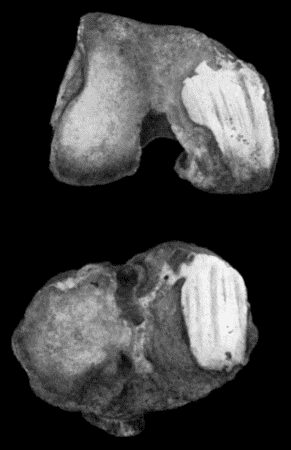

167.Loose Body from Knee-joint 541

168.Multiple partially ossified Chondromas of Synovial Membrane from Shoulder-joint 542

169.Multiple Cartilaginous Loose Bodies from Knee-joint 543